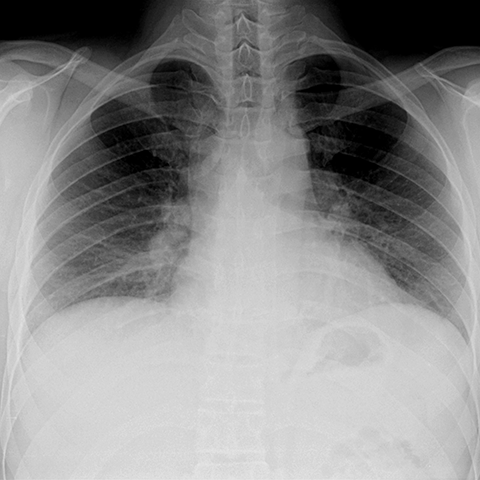

Normal PA Chest Radiograph on Expiration [2 of 2]